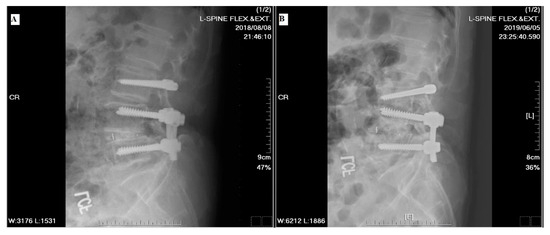

2.2. Radiological Evaluation

3.5. Motion Angular Change

4. Discussion